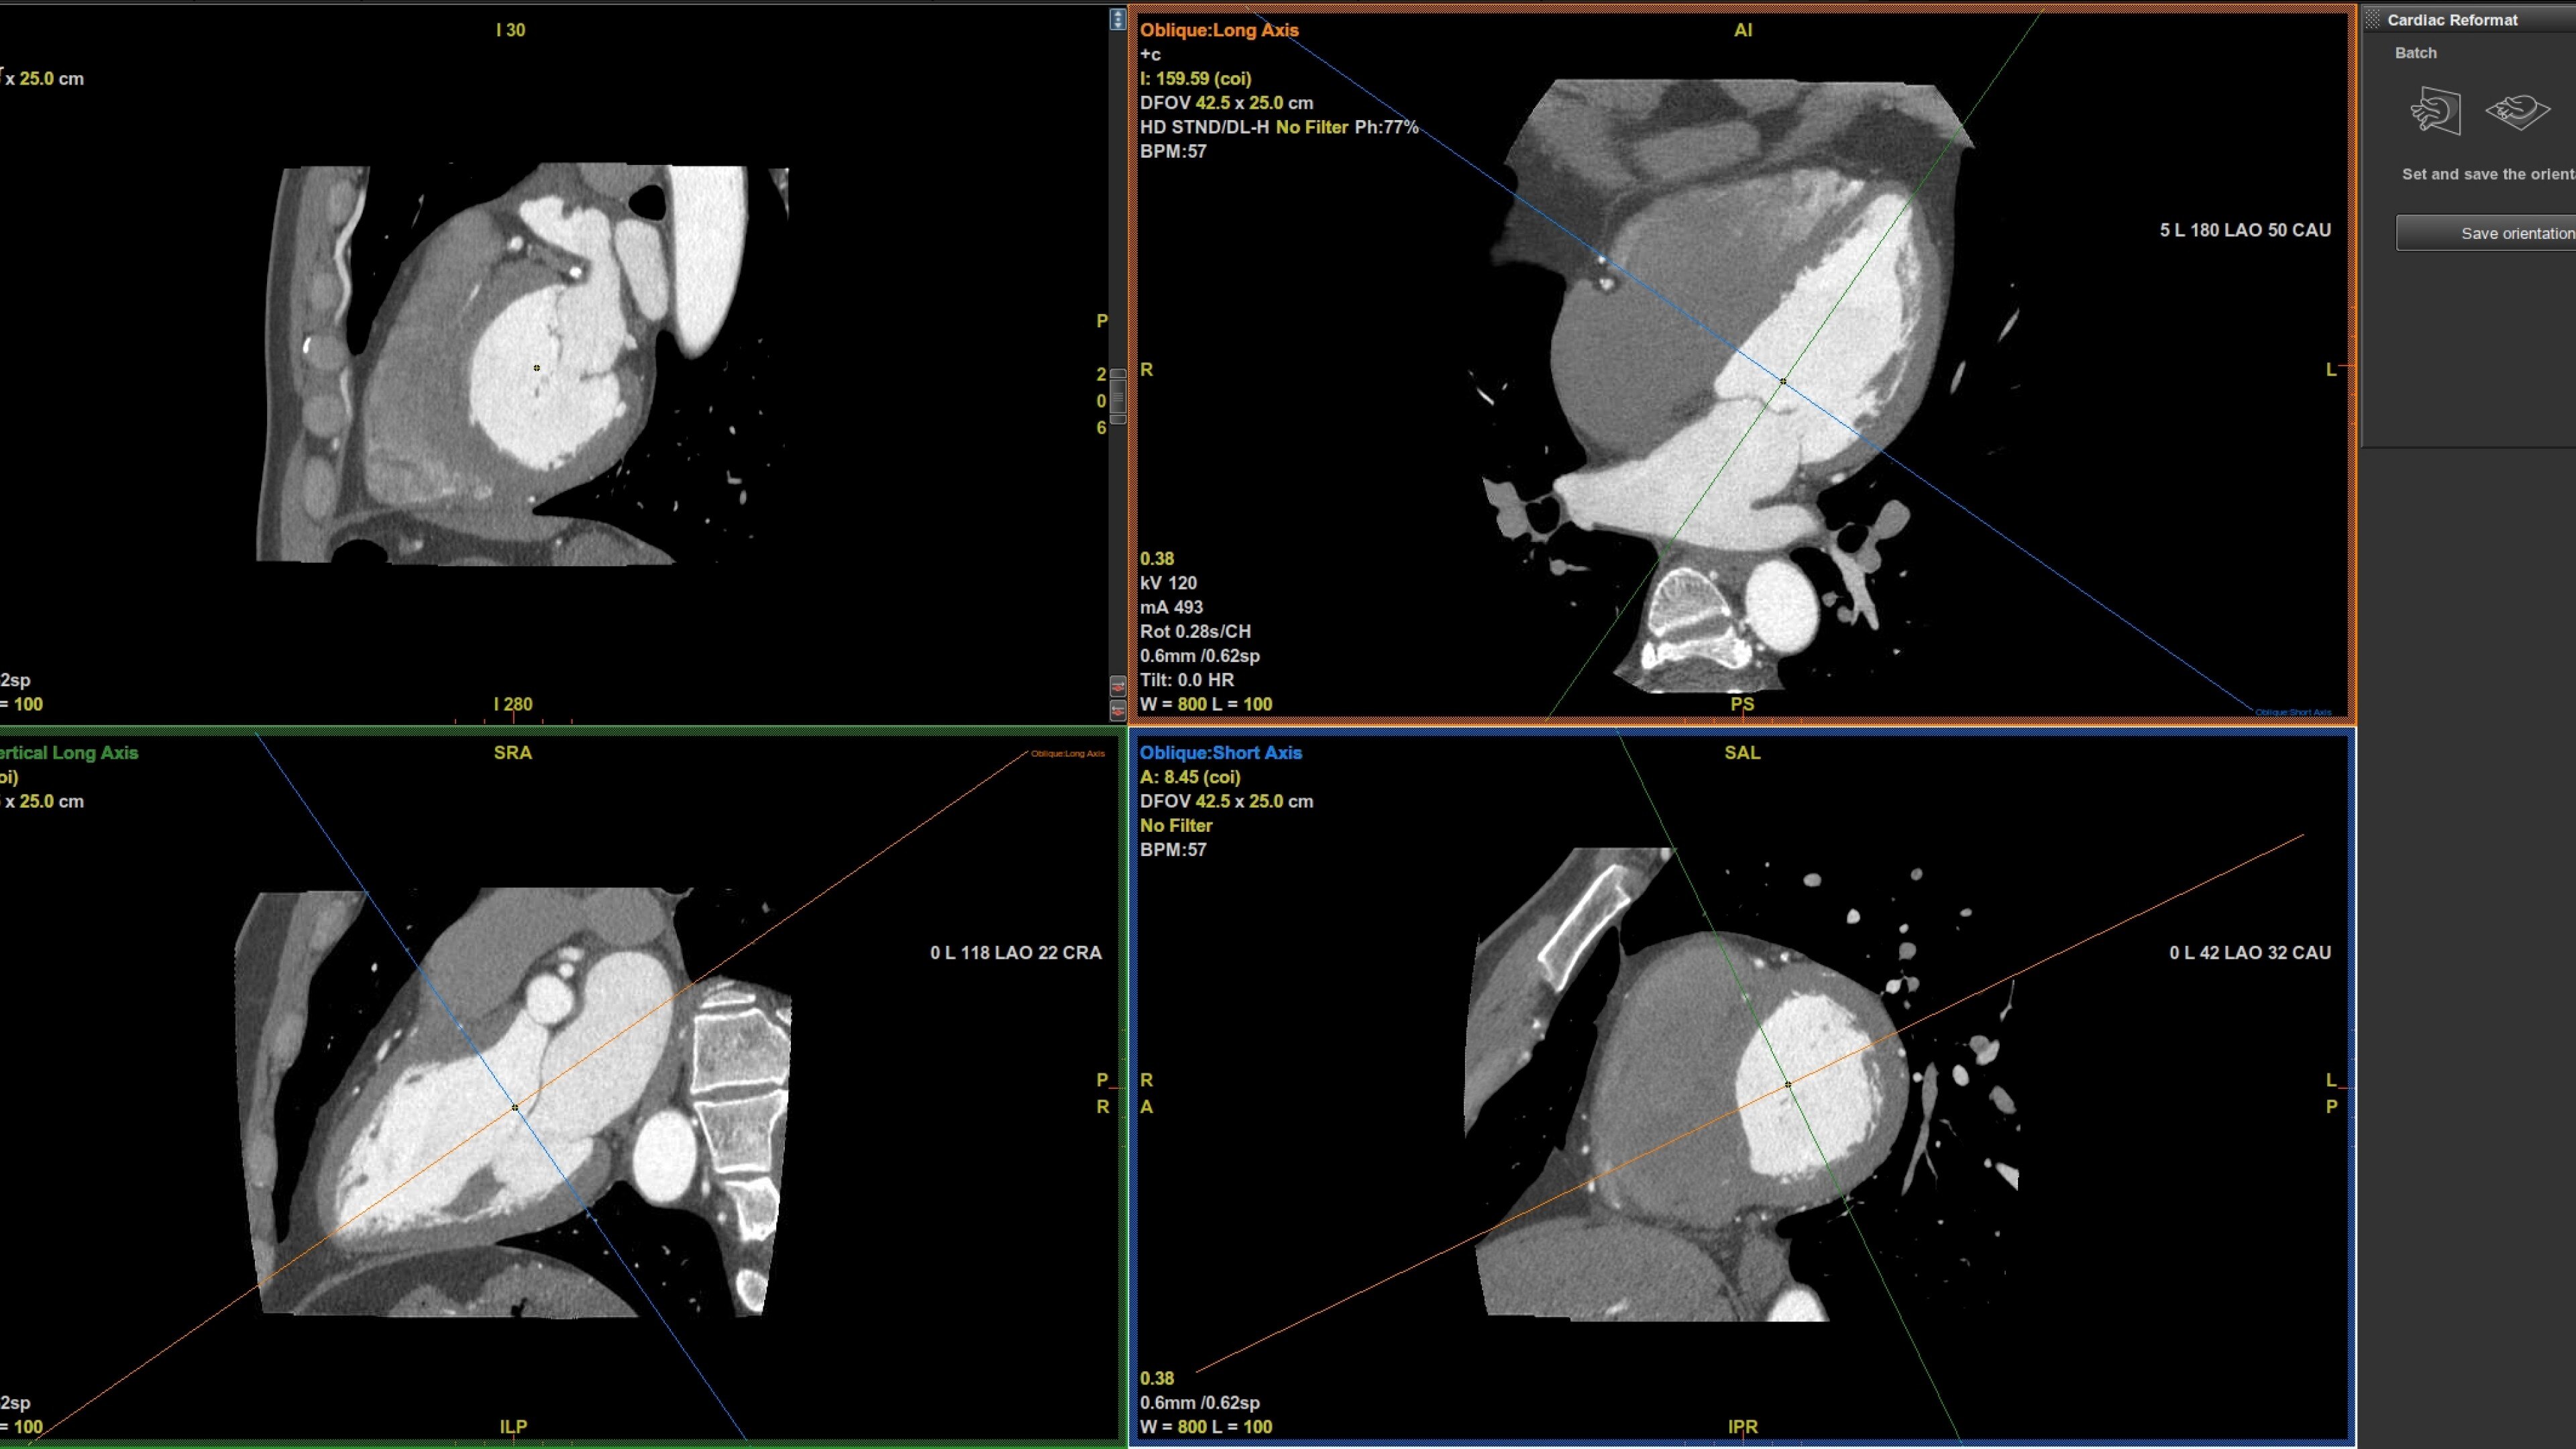

• Auto Coronary analysis automatically segments the coronary tree, tracks and labels the coronary arteries

• Three pre-defined orientation protocols for easy review of the coronary vessels and chambers